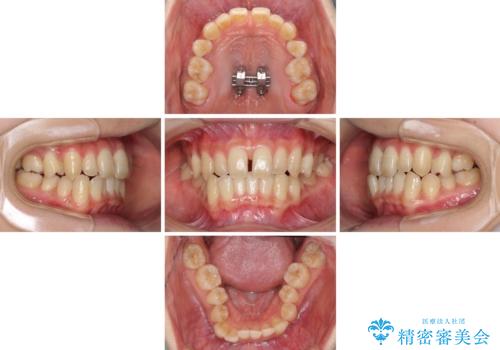

反対咬合は上顎骨の幅が下顎骨よりも小さいことが原因なので、拡大装置により骨幅を広げて上下関係を改善し、その後インビザラインにて歯並びを整えることとしました。

上顎骨を拡大したことで前歯に隙間ができ、1ヶ月ほど恥ずかしい時期がありましたが、しっかりとした咬み合わせに仕上がり、患者様には大変満足していただきました。